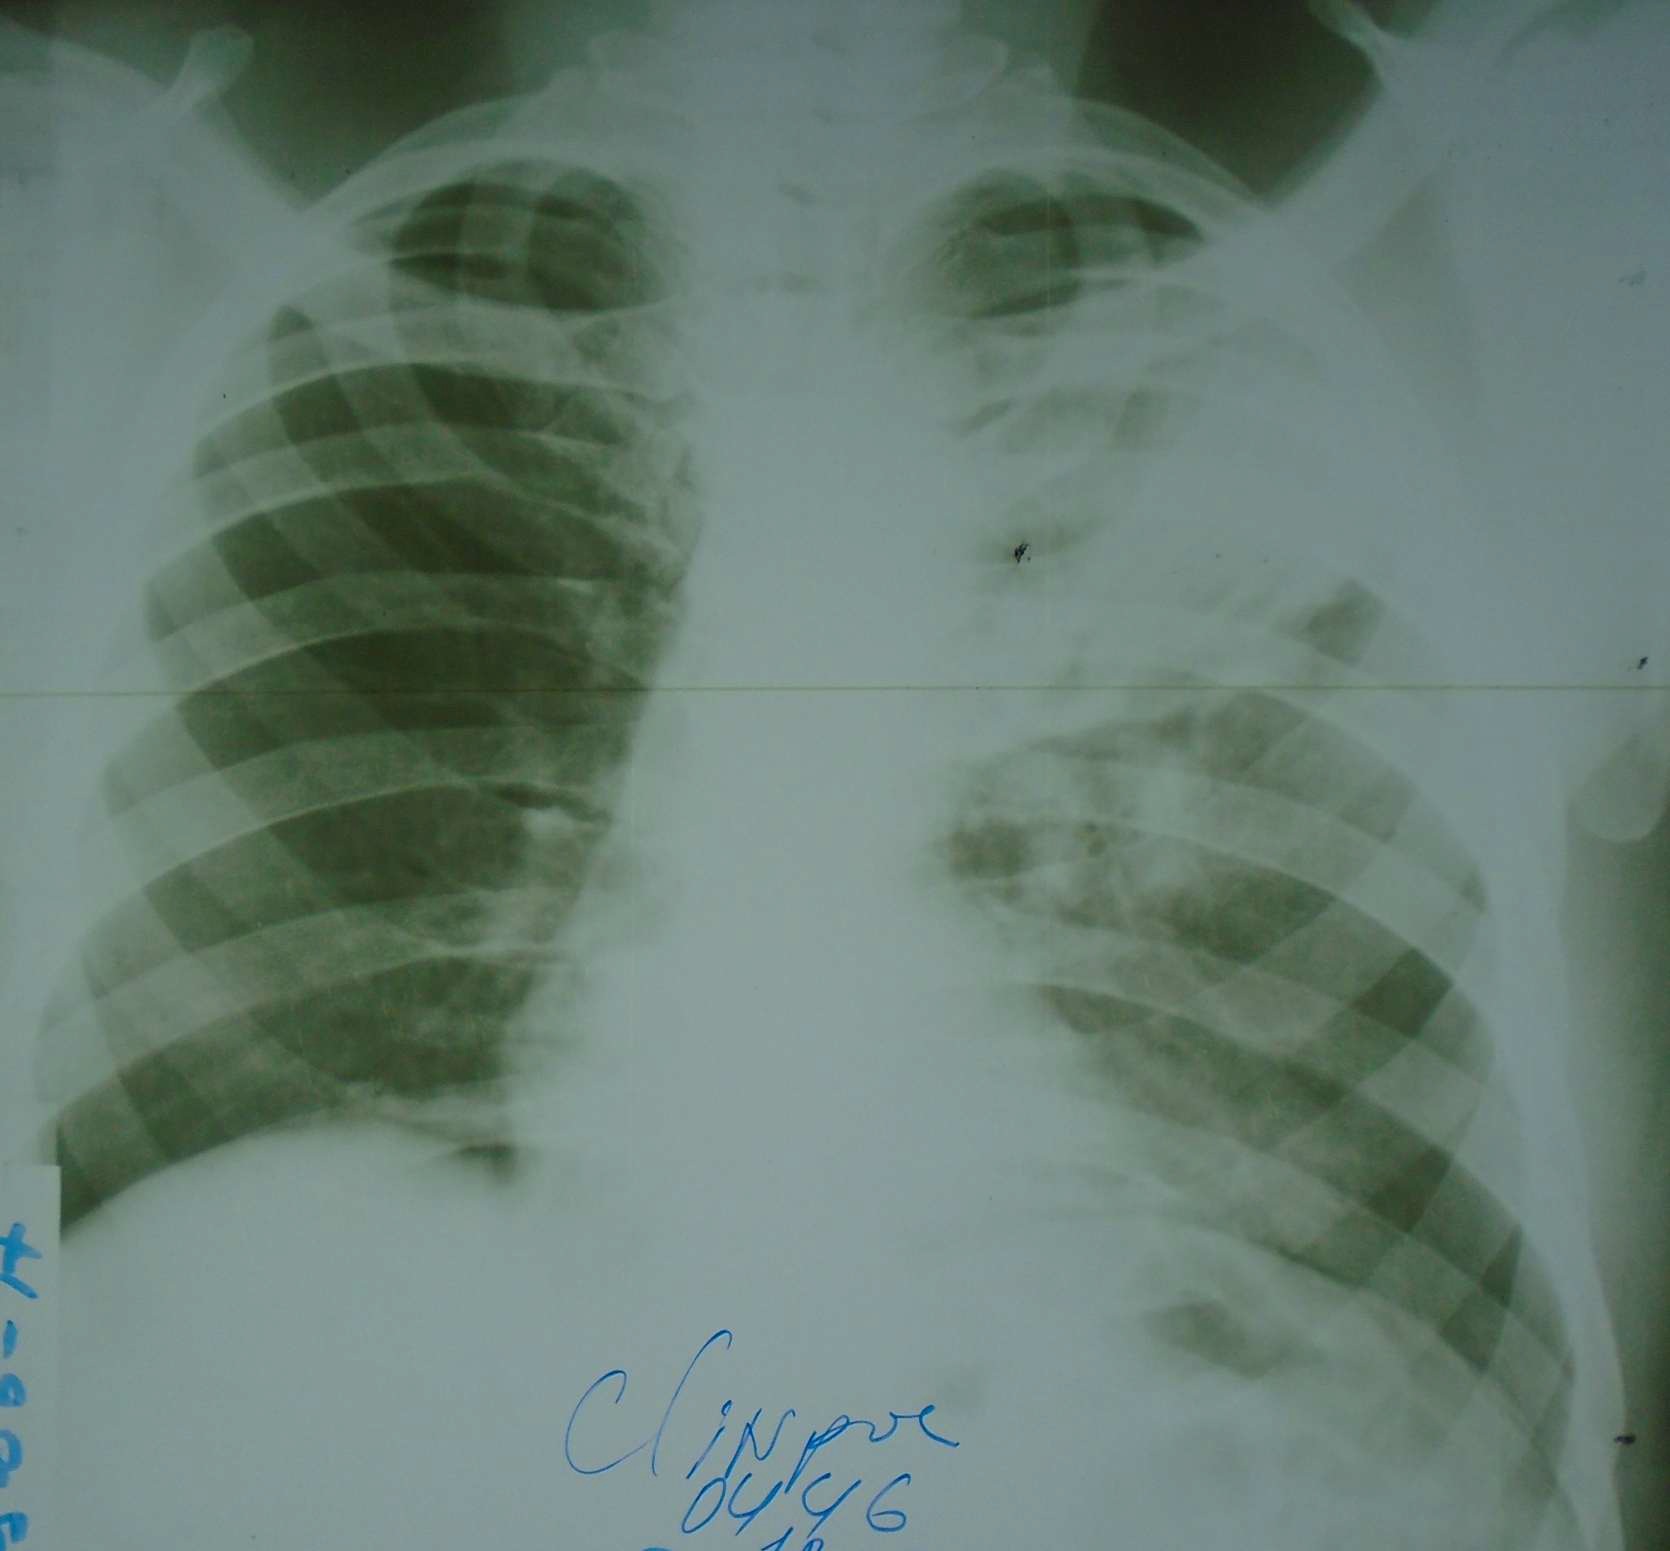

AI detects tuberculosis on photos of chest x-rays

Mobile phone-based analog radiographic image analysis could represent an easily implementable tool.